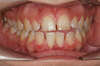

Béance traitée par gouttières

Début du traitement

Fin du traitement